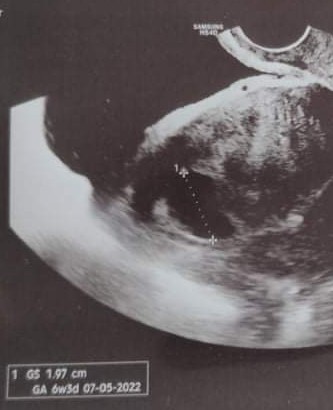

O boże boże.. Z tego co piszecie i z tego co wyczytałam, to cp przy tak niskiej becie nikt nie zobaczy.. Opcje są dwie.. Albo były dwa i coś z jedyn poszło nie tak, albo cp, albo jeszcze cos innego.. Nic czekam do jutra nic nie wymyślęja byłam w ciąży pozamacicznej w 9 tygodniu bo wcześniej lekarz powiedział że pęcherzyk jest w macicy .pojechałam do innego A tam od razu było wiadomo jak trafiłam ma stół to już miałam krwotok wewnętrzny. To była moja 3 pozamaciczna! Teraz jestem w ciąży Ale dzięki in vitro 13 lat walczyłam by zostać mama